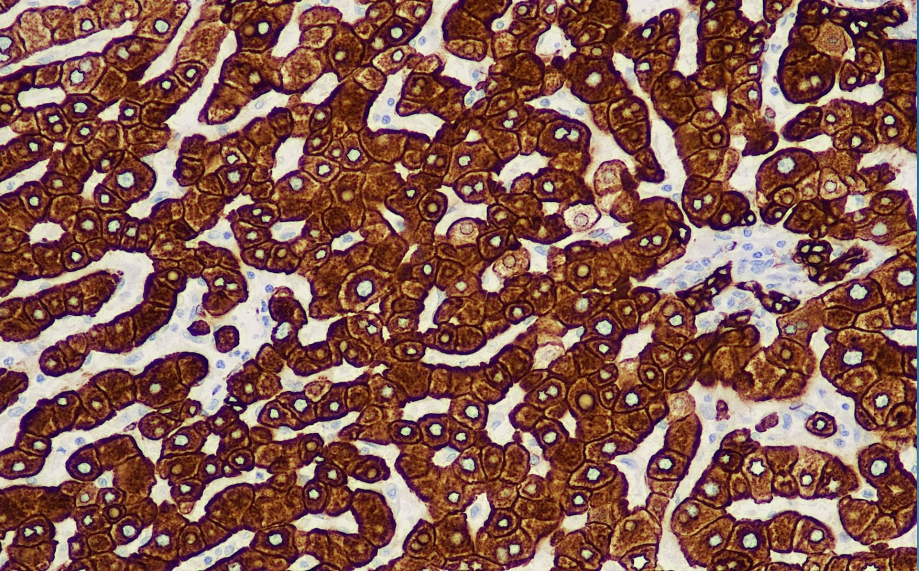

Positive control: Liver

CK35βH11 stains many ductal and glandular epithelia, but does not stain squamous epithelium, and does not react with skeletal muscle or nerve cells. This antibody is primarily used in the study of ductal carcinoma and adenocarcinoma.

The low molecular weight cytokeratin antibody reagent specifically binds to the low molecular weight cytokeratin molecular antigen. The immunohistochemistry kit containing the low molecular weight cytokeratin antibody reagent is suitable for the auxiliary diagnosis of ductal carcinoma and adenocarcinoma.